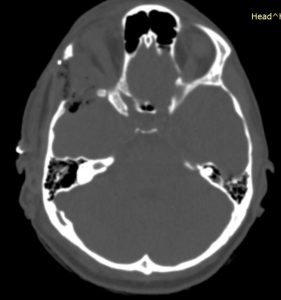

Η μετεγχειρητική αξονική τομογραφία εγκεφάλου ανέδειξε τη γενναιόδωρη αποσυμπίεση του κόγχου.

Μετεγχειρητικά η ασθενής παρουσίαζε άριστη νευρολογική εικόνα, χωρίς καμία επιδείνωση της όρασης.